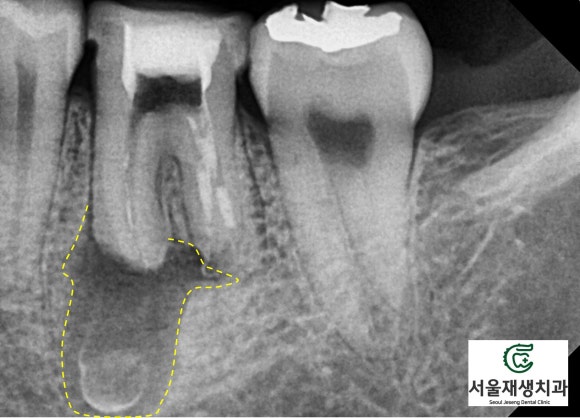

위에 소개된 세 케이스 모두 병소의 크기가 큰 편이었으나,

꾸준한 치료로 모두 새생명을 얻었답니다^^

<병소가 큰 재신경치료 케이스의 비포 애프터>

(8개월 소요)